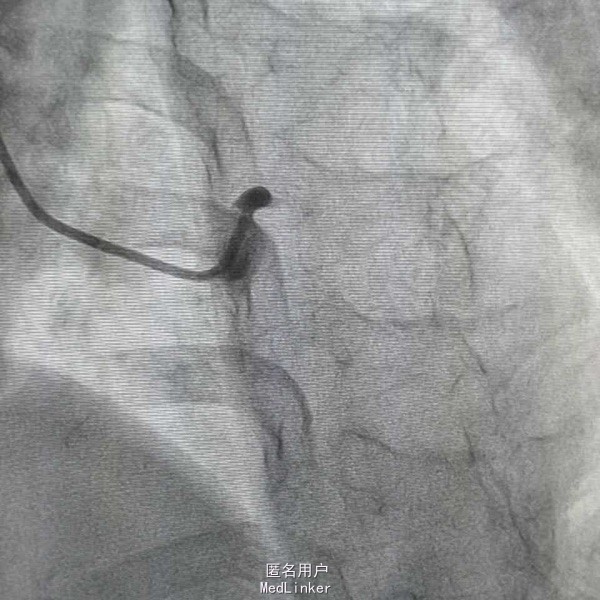

患者,女性,63岁,主因阵发性胸痛5天,加重15小时入院,既往否认高血压糖尿病史,无食物及药物过敏史,无不良嗜好。入院前一天剧烈胸痛晕厥一次,具体情况不详。

血压97/57mmHg,神清语明,口唇无发绀,颈静脉无怒张,双肺无啰音,心率82次每分,律齐,未闻及杂音,腹平软,肝脾未及,双下肢不肿。 辅查心电Il Ill avf ST段下移,avl V6 ST段抬高 白细胞14X109/L,D二聚体665ug/L,肌钙4.1ng/mL,

急性心肌梗死 心功能I级 处理,抗凝抗聚后行PCI治疗

造影示左主干闭塞,如图,预扩后快速送入支架行冠脉再通,此病人心电图很难判断左主干病变,值得警惕